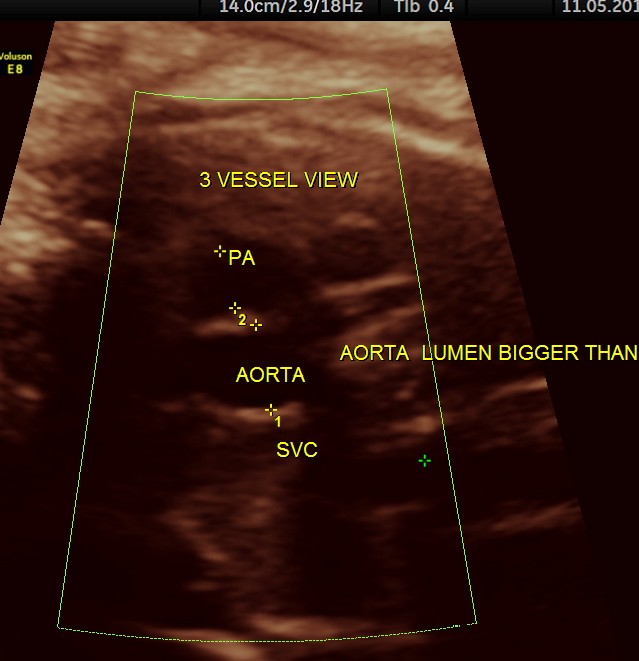

the three vessel view shows a narrow pulmonary artery compared to the aorta with flow reversal